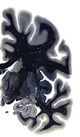

Hi-Resolution Sections · Cells (Nissl Staining) · Virtual Microscopy

Frontal sections (Nissl) from the Atlas Brain: Gallery Slice Single